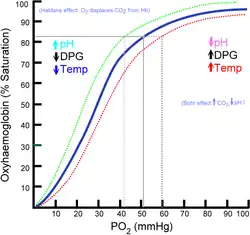

About 98.5%[22] of the oxygen in a sample of arterial blood in a healthy human breathing air at sea-level pressure is chemically combined with the hemoglobin. About 1.5% is physically dissolved in the other blood liquids and not connected to hemoglobin. The hemoglobin molecule is the primary transporter of oxygen in mammals and many other species. Hemoglobin has an oxygen binding capacity between 1.36 and 1.40 ml O2 per gram hemoglobin,[23] which increases the total blood oxygen capacity seventyfold,[24] compared to if oxygen solely were carried by its solubility of 0.03 ml O2 per liter blood per mm Hg partial pressure of oxygen (about 100 mm Hg in arteries).[24]

Under normal conditions in adult humans at rest, hemoglobin in blood leaving the lungs is about 98–99% saturated with oxygen, achieving an oxygen delivery between 950 and 1150 ml/min[25] to the body. In a healthy adult at rest, oxygen consumption is approximately 200–250 ml/min,[25] and deoxygenated blood returning to the lungs is still roughly 75%[26][27] (70 to 78%)[25] saturated. Increased oxygen consumption during sustained exercise reduces the oxygen saturation of venous blood, which can reach less than 15% in a trained athlete; although breathing rate and blood flow increase to compensate, oxygen saturation in arterial blood can drop to 95% or less under these conditions.[28] Oxygen saturation this low is considered dangerous in an individual at rest (for instance, during surgery under anesthesia). Sustained hypoxia (oxygenation less than 90%), is dangerous to health, and severe hypoxia (saturations less than 30%) may be rapidly fatal.[29]

A fetus, receiving oxygen via the placenta, is exposed to much lower oxygen pressures (about 21% of the level found in an adult's lungs), so fetuses produce another form of hemoglobin with a much higher affinity for oxygen (hemoglobin F) to function under these conditions.[30]

Hemoglobin, the main oxygen-carrying molecule in red blood cells, carries both oxygen and carbon dioxide. However, the CO2 bound to hemoglobin does not bind to the same site as oxygen. Instead, it combines with the N-terminal groups on the four globin chains. However, because of allosteric effects on the hemoglobin molecule, the binding of CO2 decreases the amount of oxygen that is bound for a given partial pressure of oxygen. The decreased binding to carbon dioxide in the blood due to increased oxygen levels is known as the Haldane effect, and is important in the transport of carbon dioxide from the tissues to the lungs. A rise in the partial pressure of CO2 or a lower pH will cause offloading of oxygen from hemoglobin, which is known as the Bohr effect.